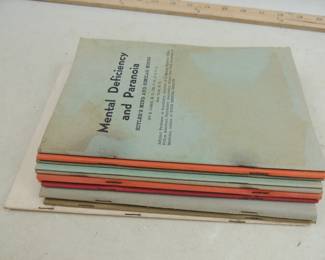

1017 - Lot of Assorted Booklets, Pamphlets and MORE

3038 - Lot of Assorted Booklets Pamphlets

3039 - Lot of Vinage Booklets Pamphlets

3040 - Lot of Booklets Pamphlets